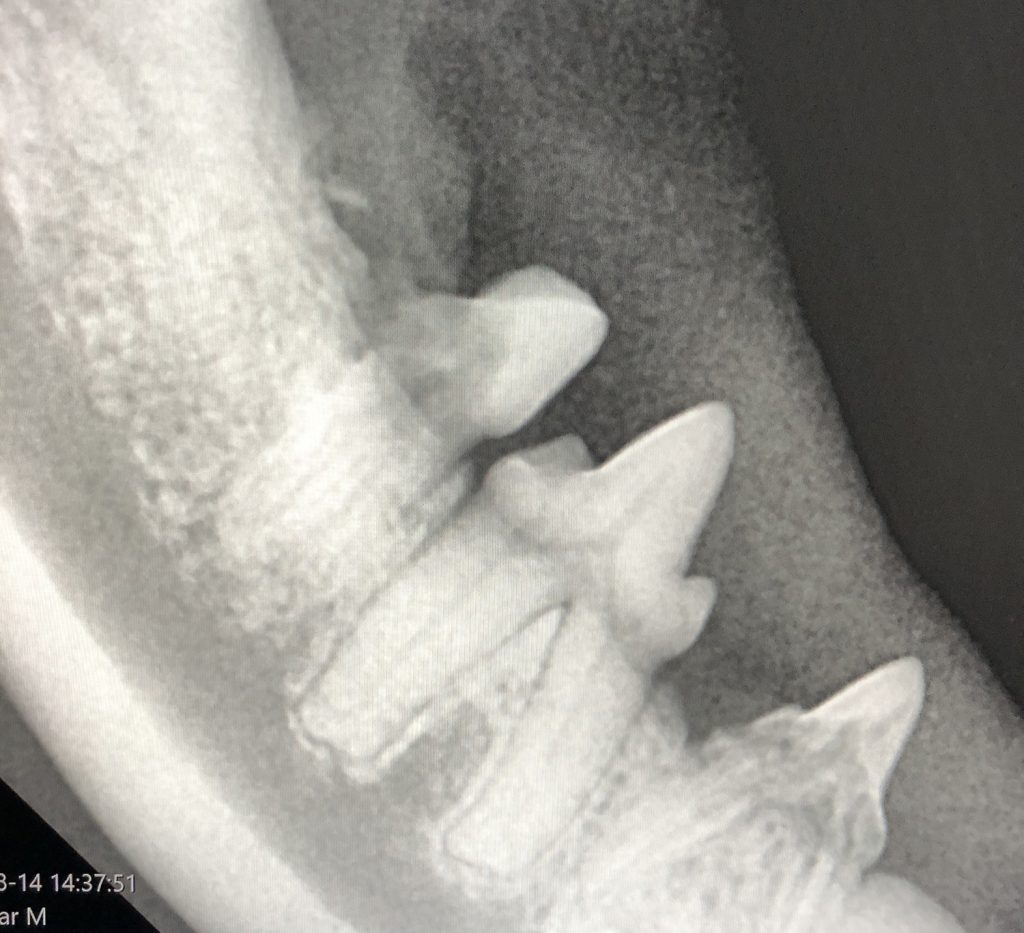

Op de foto kan goed weergegeven worden of er aantasting is van het bot rondom een wortel of dat er terugtrekking van het bot rondom de tand of kies zichtbaar is. Als deze terugtrekking te ver is gevorderd, is het noodzakelijk de tand of kies te trekken, aangezien de ondersteuning van de tand te zwak wordt. Een ander voordeel van deze manier van röntgenfoto’s maken tijdens een gebitsbehandeling is dat er gecontroleerd kan worden of wortels van tanden en kiezen überhaupt nog aanwezig zijn. Dit voorkomt onnodig zoeken in een tandkas, als van tevoren al blijkt dat er niets meer aanwezig is.

Voornamelijk bij de kat bestaat de aandoening Feline Odontoclastic Resorptive Lesions, waarbij de tanden en kiezen net onder het tandvlees worden aangetast. Dit zorgt voor pijnlijkheid bij het kauwen en kan de volledige wortel oplossen. Op de dentale röntgenfoto kan deze aandoening zeer goed zichtbaar worden gemaakt, zodat het probleem op de juiste manier kan worden aangepakt.